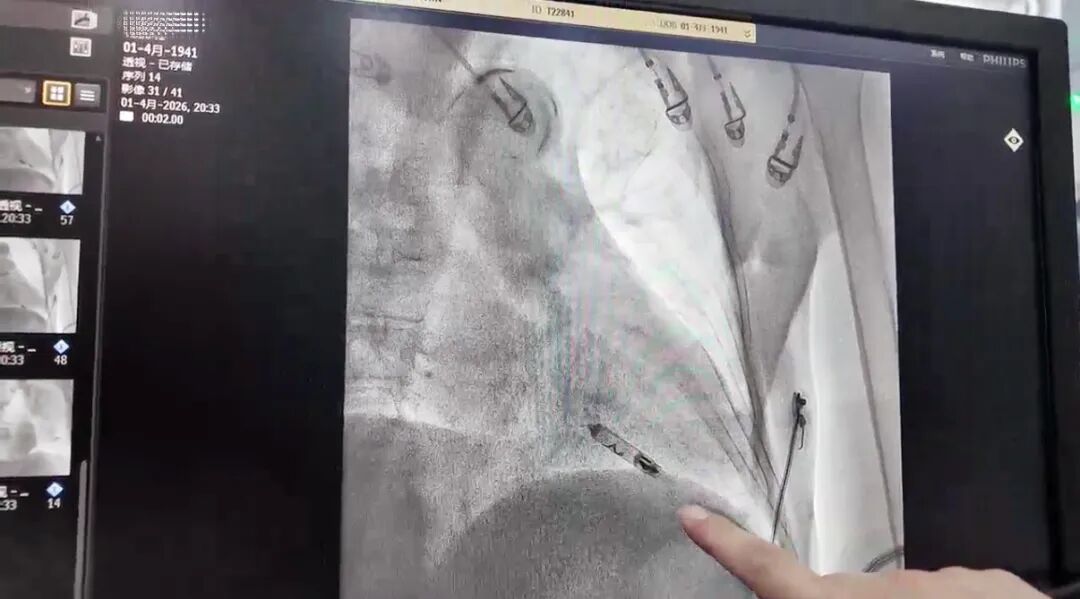

此次救治始于康养中心的一次突发状况:老人在日常康养期间突发晕厥倒地。康养医护第一时间启动应急响应并完成初步评估,随即邀请脑科专家紧急会诊。脑科团队迅速完善神经系统检查,凭借细致的鉴别诊断,精准排除了脑血管疾病,锁定晕厥“元凶”——长达6.7秒的心脏停搏(严重心律失常)。明确诊断后,老人立即转入心内科,一场与时间赛跑的心脏救治随即展开。